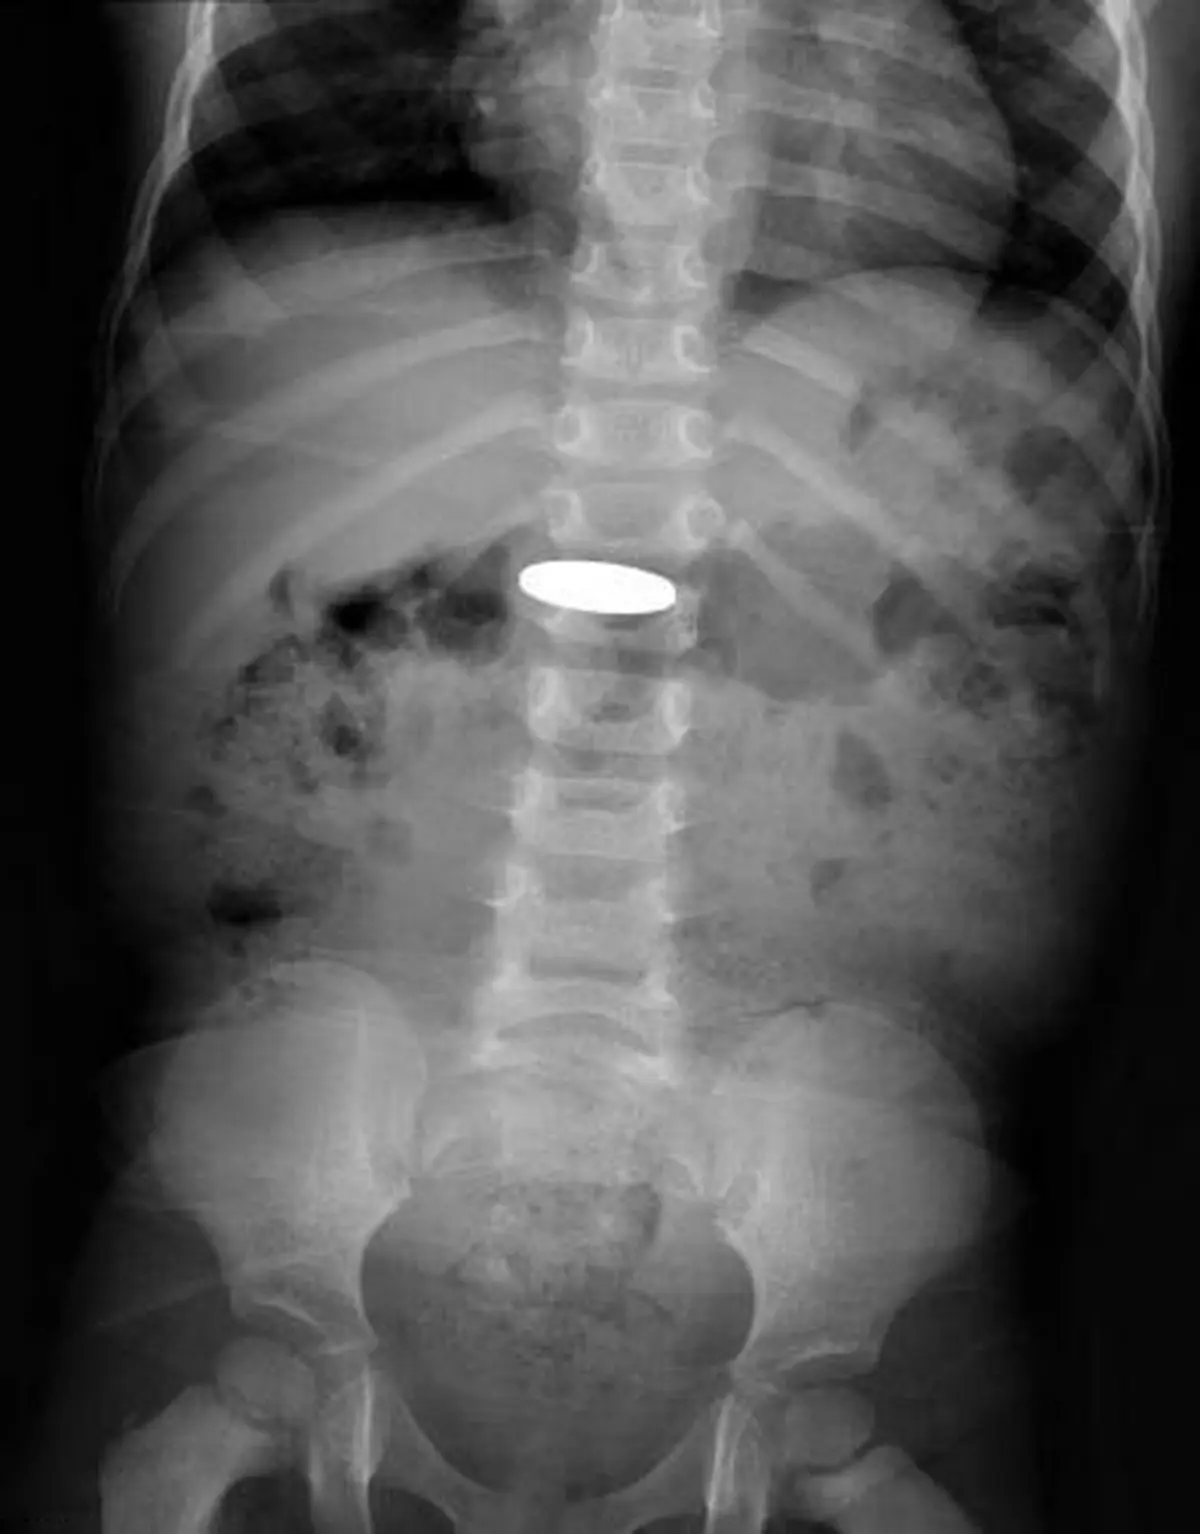

رکنا: پژوهشگران آمریکایی در بررسی جدیدی دریافتند کودکانی که باتری دکمهای را میبلعند، در معرض آسیب شدید معده قرار دارند.

به گزارش مدیکالاکسپرس، بلعیدن باتریهای دکمهای توسط کودکان، میتواند به غشای مخاطی معده آنها آسیب برساند؛ در نتیجه حتی اگر نشانههای خطرناکی در کودک دیده نشود و باتری بدون خطر از مری عبور کند، پزشکان باید فوراً آن را خارج کنند.

"راچا خلف"(Racha Khalaf)، پژوهشگر ارشد این پروژه گفت: ما میدانیم حتی بدون وجود نشانههای خطرناک نیز امکان آسیب رسیدن وجود دارد. ورود باتری به معده میتواند به آسیبهایی از جمله سوراخ شدن دیواره معده منجر شود؛ در نتیجه پزشکان باید باتری را به سرعت خارج کنند تا نتواند از دستگاه گوارش عبور کند.

پژوهشگران بیمارستانهای کودکان در کلرادو، فلوریدا، تگزاس و اوهایو، دادههای مربوط به ۶۸ مورد بلعیدن باتری را از ژانویه ۲۰۱۴ تا مه ۲۰۱۸ گردآوری کردند. پیش از این نیز پژوهشهایی در مورد ورود باتری دکمهای به مری انجام شده بودند اما اطلاعات کمی در مورد تأثیر باتری بر معده در بر داشتند.

خلف ادامه داد: ما موارد بسیاری از آسیبهای ناشی از باتری دکمهای را دیدهایم. این باتریها، در اسباببازیها، کنترلها و ابزاری از این دست به کار میروند؛ در نتیجه همه جا وجود دارند.

وی افزود: ما در ۶۰ مورد از موارد تحت بررسی، آسیبهای شدید به غشای مخاطی معده را مشاهده کردیم که نشانه آشکاری در فرد به جا نگذاشته بودند. این موضوع نشان میدهد که پزشکان و والدین نباید منتظر بروز نشانه خاصی بمانند و باید به سرعت نسبت به خارج کردن باتری اقدام کنند. این کار میتواند نیاز به مراجعه مکرر به بخش اورژانس و عکسبرداریهای پی در پی را کاهش دهد.برای ورود به کانال تلگرام ما کلیک کنید.